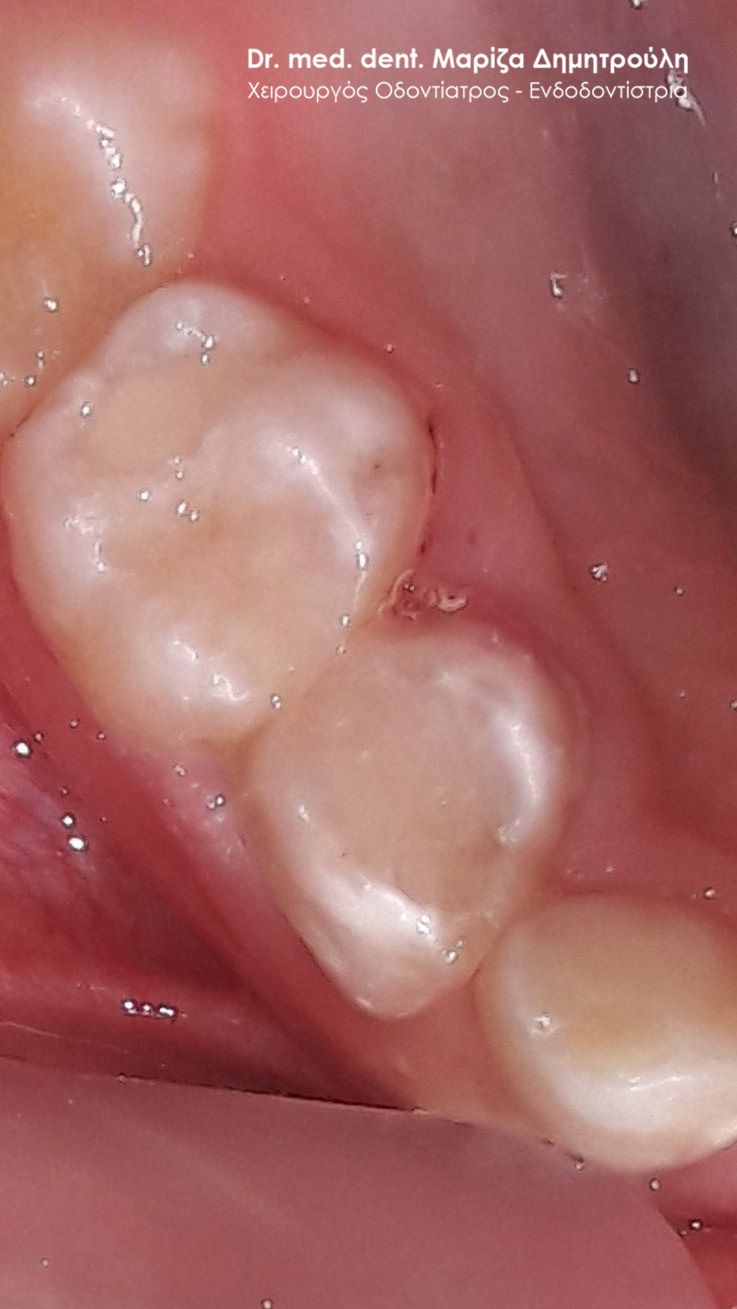

ΠΡΙΝ

ΜΕΤΑ – Σφράγισμα νεογιλού δοντιού και sealant μόνιμου δοντιού